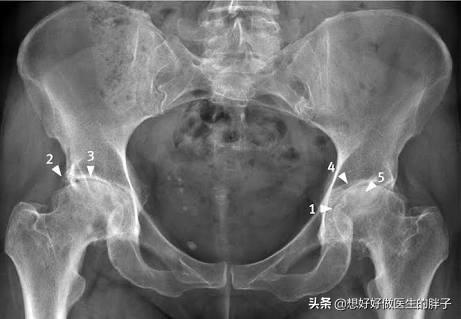

对于髋关节疼痛的朋友,我们首先应该检查骨盆的平片或者是痛一侧的髋关节正侧位片,但可以初步了解患者的关节是否存在着髋关节间隙的狭窄,是否有大量的骨赘形成以及髋关节的整体发育是否正常。如果我们发现患者的关节间隙狭窄,那么多见于股骨头的坏死或者是髋关节骨关节炎导致关节间隙软骨损伤;如果x线发现在股骨头与颈连接的部位有异常的隆起,那么很有可能患者存在的髋关节撞击综合症。